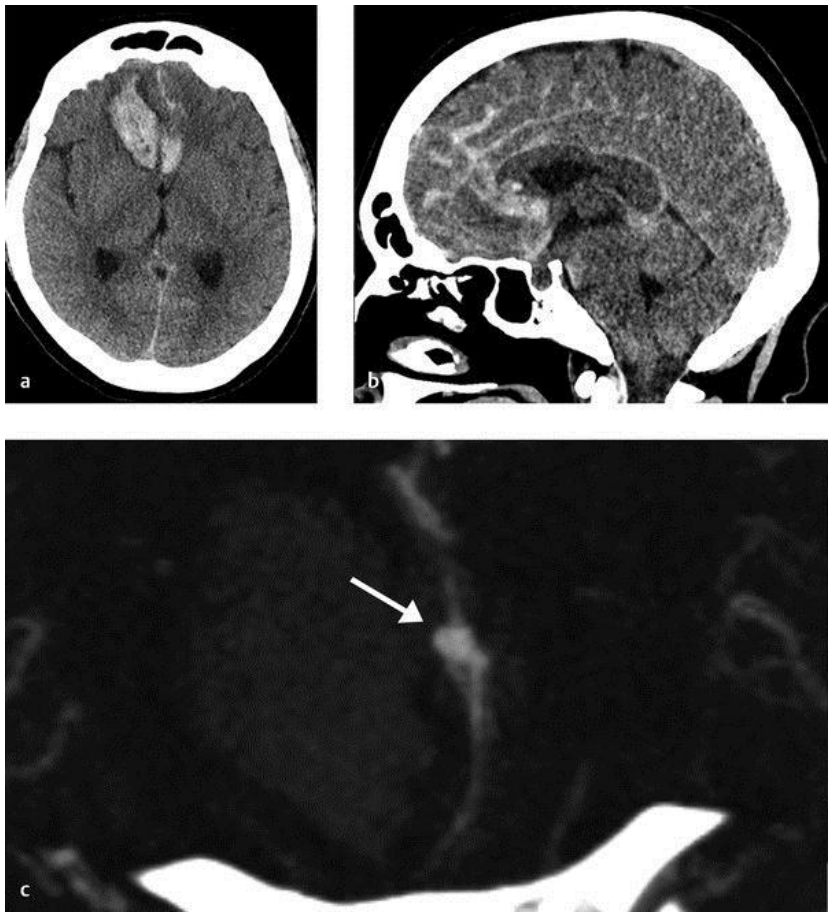

Hình ảnh xuất huyết dưới nhện và trong nhu mô não do phình mạch não vỡ

Hình ảnh xuất huyết dưới nhện và trong nhu mô não do phình mạch não vỡ (hình mũi tên chỉ trên CT mạch).